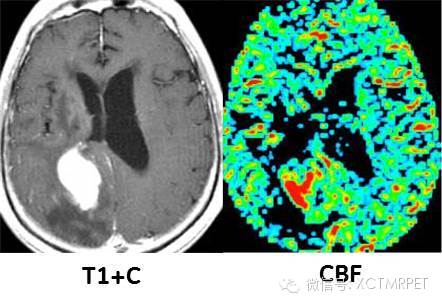

胶质瘤术后复发: T1增强图像上可见明显强化的占位肿块,周围伴低信号水肿带,PWI的CBV图像上,血供丰富的区域为复发的肿瘤组织,相比T1强化区域,对肿瘤实质定位更精确。